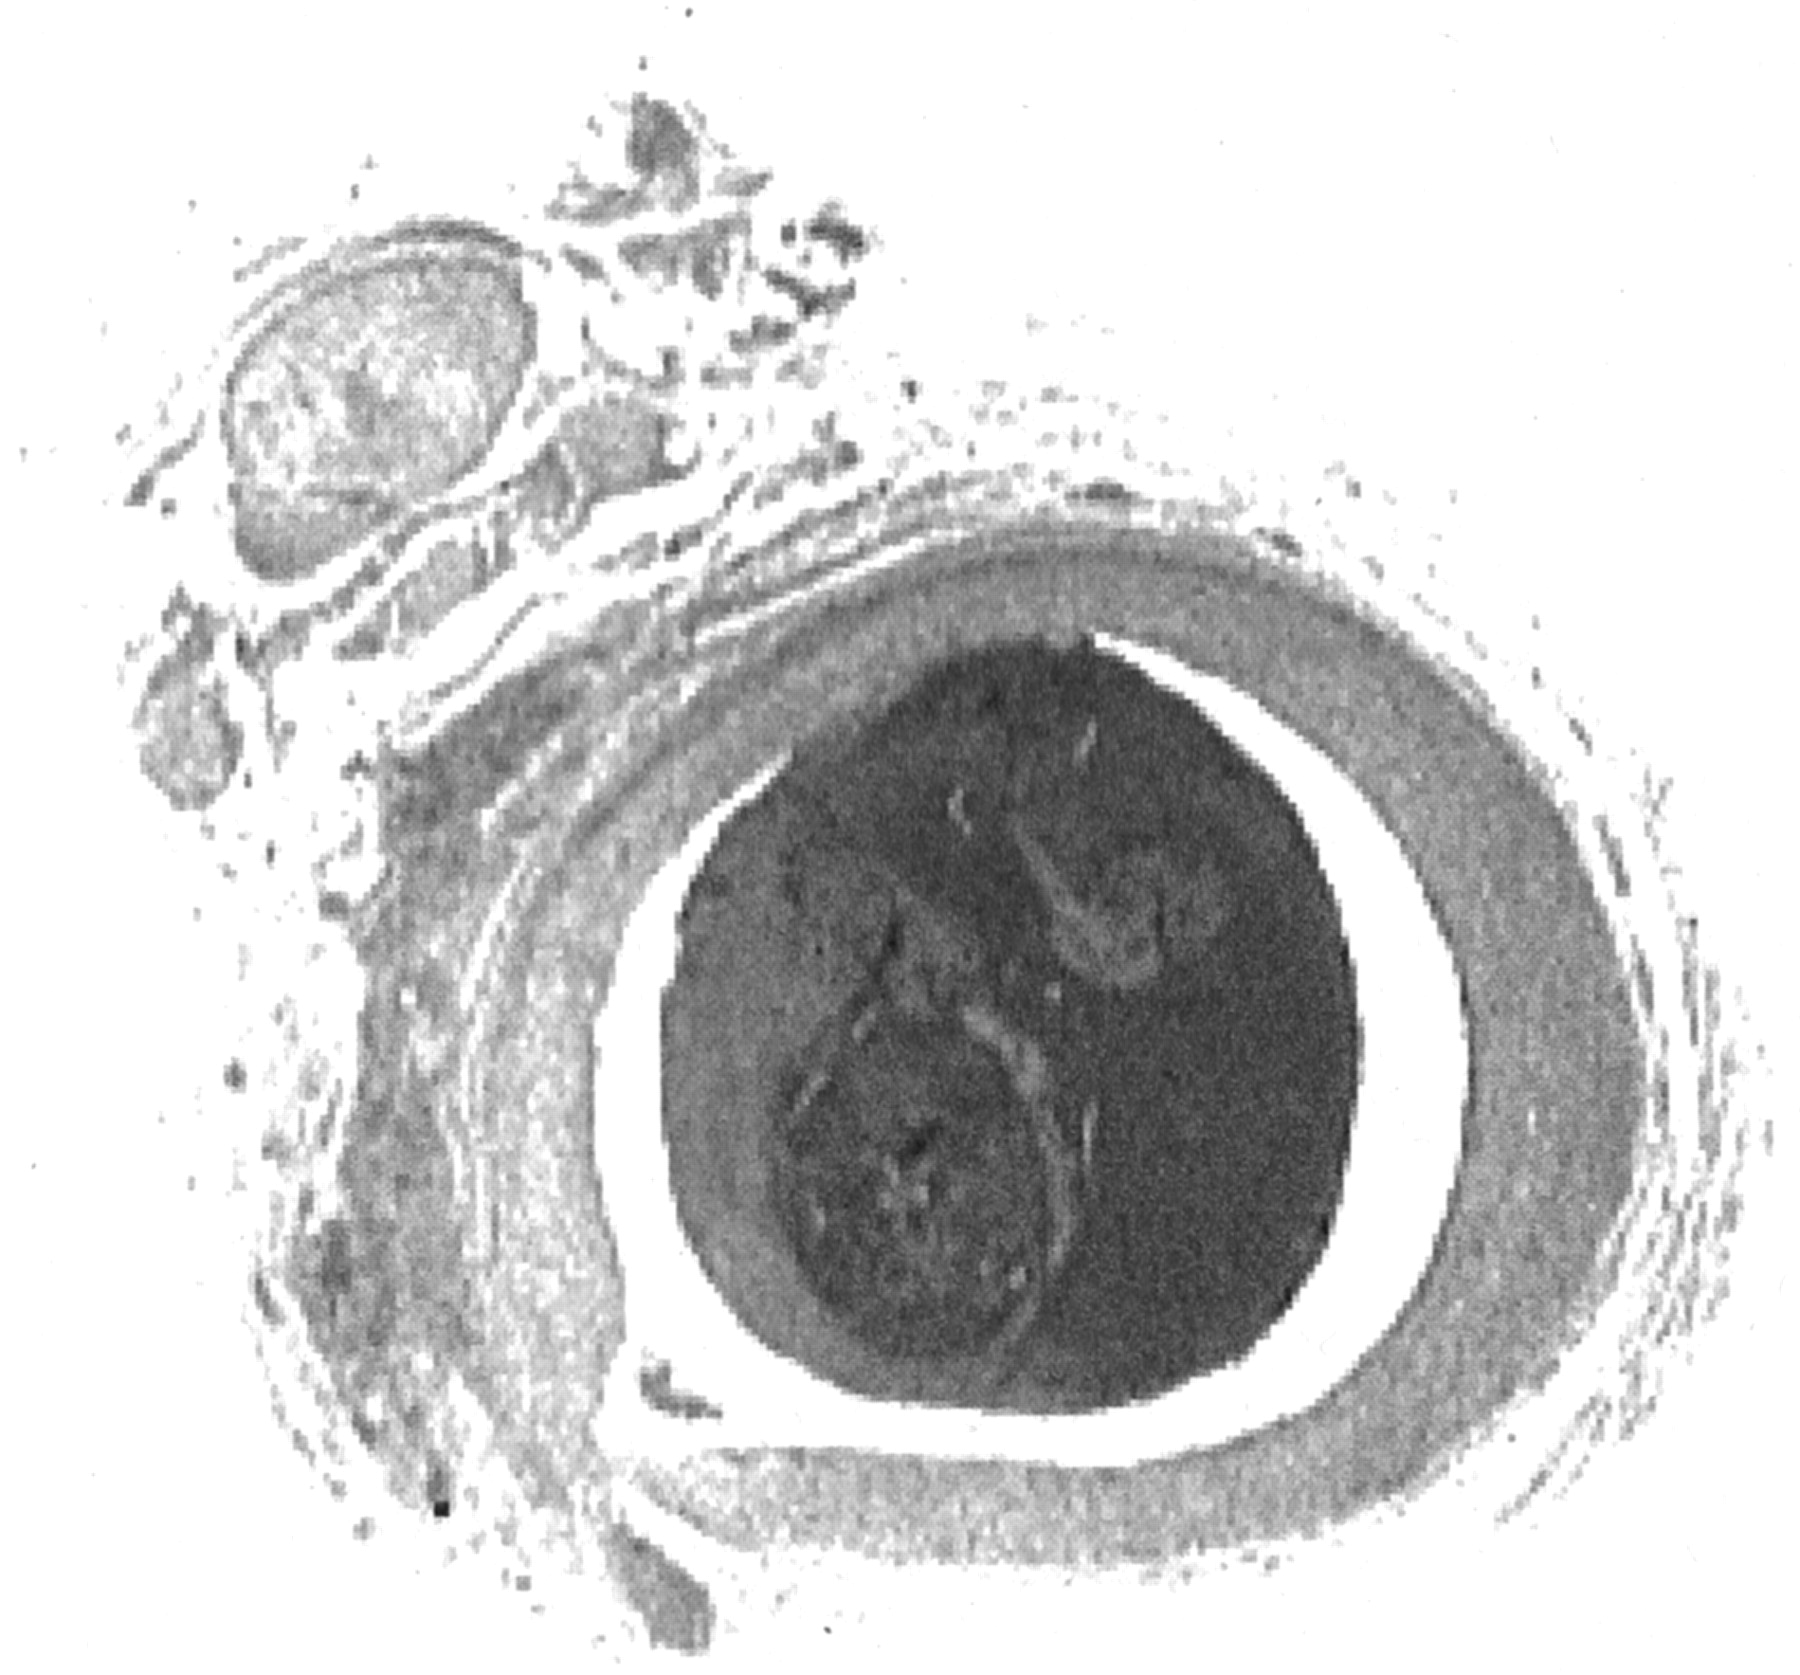

Hematoxylin and eosin staining confirmed the presence of solid, organized thrombus in each specimen (Fig 3). The endothelium was intact in each specimen, without evidence of intimal dissection, intramural thrombus, or vessel rupture.

Cross section of ascending pharyngeal artery obtained 3 hr after clot injection seen at ×15 magnification. Hematoxylin and eosin staining reveals an intact endothelium, with no evidence of vessel wall disruption or subintimal hemorrhage. Solid thrombus fills the vessel lumen.

Gross evaluation of the intraluminal clot revealed solid, thrombin-rich thrombus. The clot filled the vessel lumen entirely. No evidence of recanalization was observed.